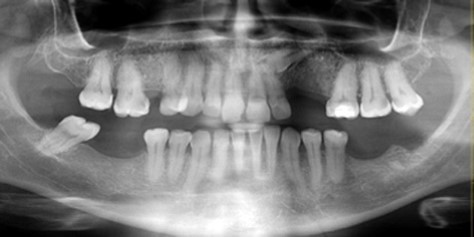

After discussing treatment options the patient refused endodontic treatment and extraction of the lower left third molar was therefore approved. Local anaesthesia was administered in the form of inferior alveolar nerve block. The temporary restoration was removed. The instrument was located and extricated from the canal with the help of fine mosquito forceps and then the tooth was extracted (Figure 4). Panoramic radiograph confirmed satisfactory removal of the broken endodontic instrument from the mandibular canal (Figure 5). The same treatment protocols reported by López-López et al., 20125 were used: the patient was prescribed with 1 mg kg -1 per day prednisone (Dacortin®,30 mg) in two doses, in a gradually reducing regimen on a daily basis, and 150 mg per day pregabalin (Lyrica®, 75 mg; Pfizer SL, Barcelona, Spain), two doses by day, monitoring the progress with periodic follow-up visits.

Figure 5.Panoramic radiographs confirmed removal of the broken endodontic instrument from the mandibular canal.